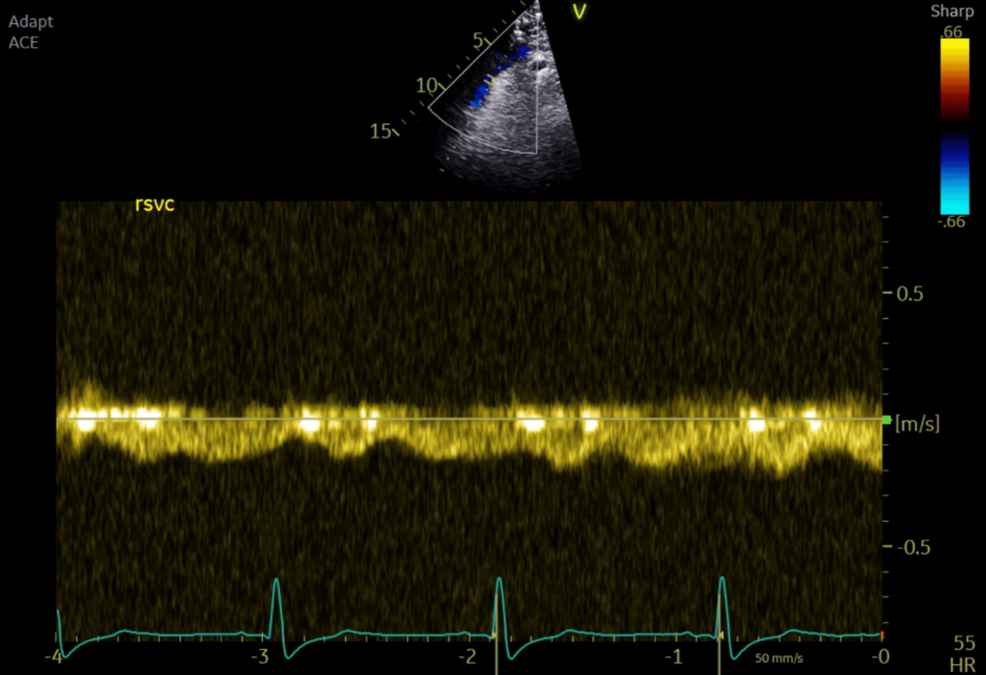

Intraoperative TOE showed good systemic ventricular function and left atrioventricular valve regurgitation. The total cavopulmonary connection (TCPC) demonstrated laminar flow in both caval pathways, with blunting and cessation of forward flow during positive pressure inspiration (Figures 1–2).